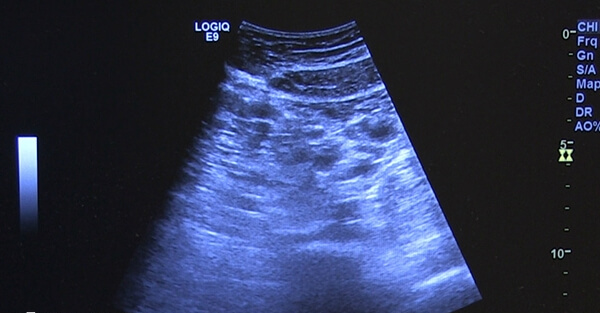

窦卵泡计数(AFC)是指在行妇科超声检查的时候,对卵巢中的窦卵泡数量进行计数,一般是在月经期第2-3日进行。是对女性卵巢中直径2-9mm左右的卵泡数目进行测量。这种卵泡处于周期中卵泡发育的早期阶段,是成熟卵泡的发育基础。

窦卵泡数可以很好地评估女性体内剩余的活卵数量,以估计未来的生育能力。正常女性通过B超一般可以数到7-8个甚至10多个窦卵泡,当双侧卵巢里窦卵泡数量≤6个,提示卵巢储备功能下降,预测卵巢低反应。